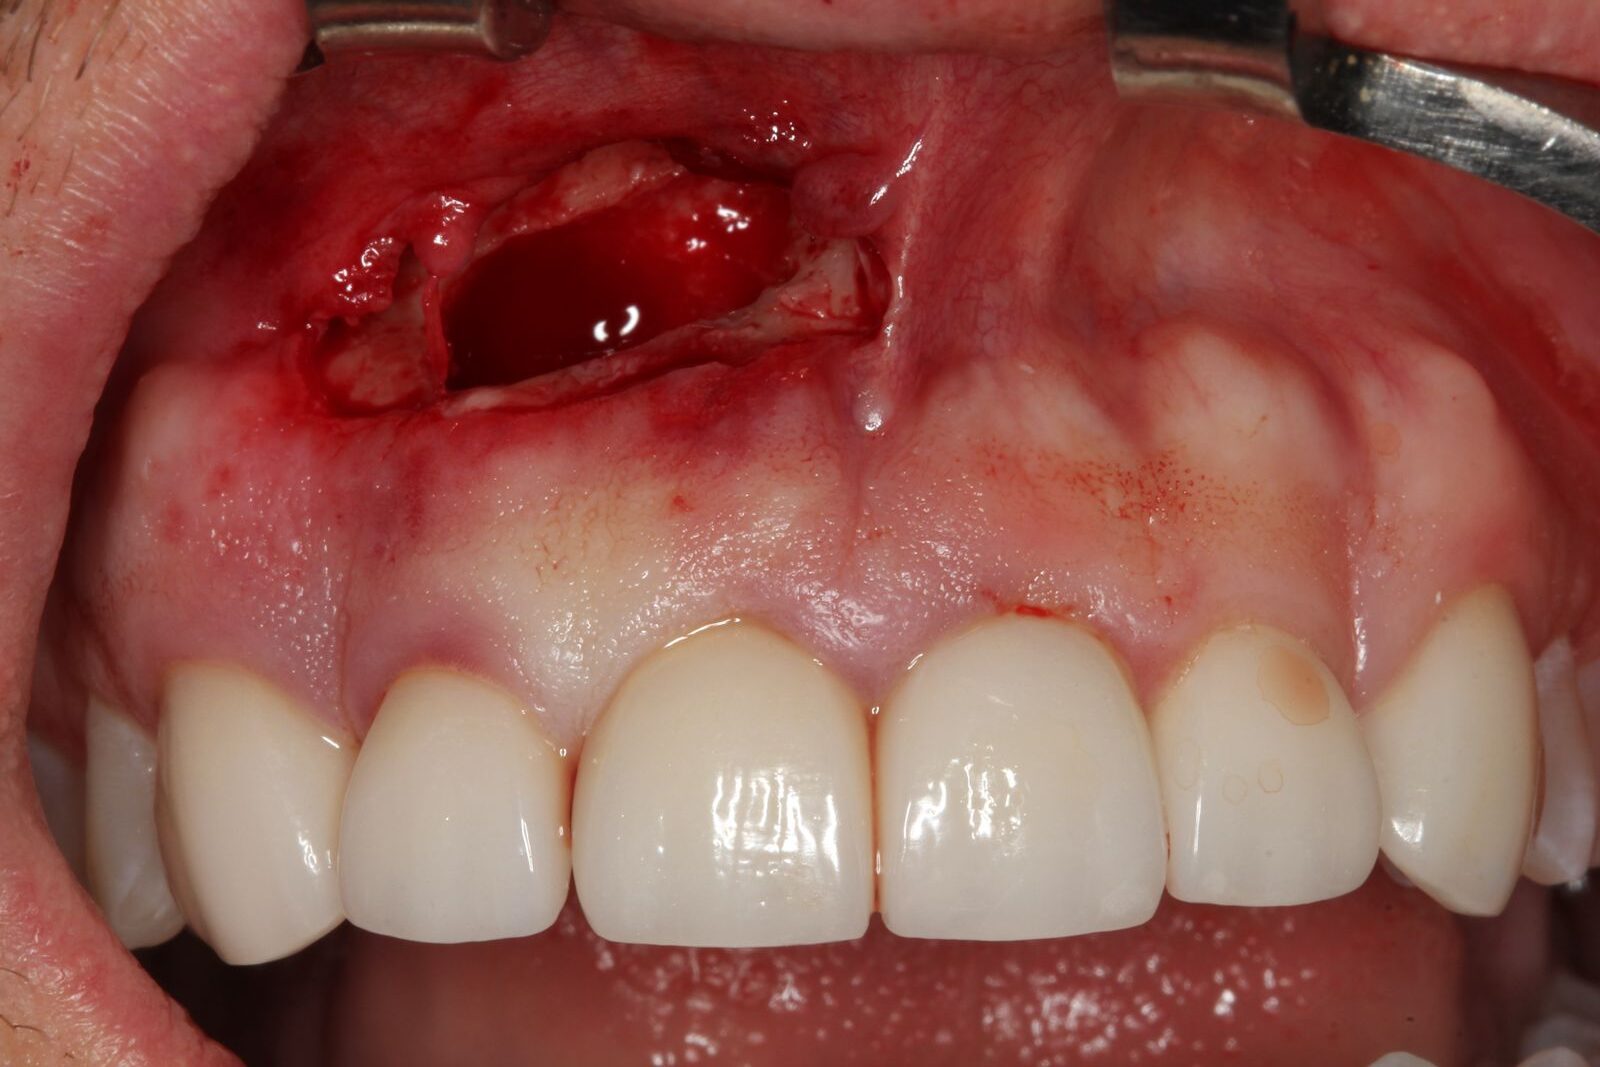

Uma incisão na gengiva com bisturi, permitindo acesso à região óssea. A exposição da área infectada muitas vezes já revela a gravidade da lesão, seguida da drenagem do conteúdo infeccioso, quando presente.

Depois, é feita uma curetagem cuidadosa, removendo todo o tecido inflamado ou contaminado ao redor da raiz e o corte da ponta do ápice radicular, eliminando a porção comprometida. Com a área limpa, pode-se aplicar o enxerto ósseo, geralmente com biomaterial associado a técnicas modernas de regeneração.

No caso clínico descrito, foi utilizado um enxerto com fibrina rica em plaquetas (PRF) misturado com cerabone (osso), combinação que favorece a cicatrização, estimula a regeneração óssea e melhora o prognóstico do tratamento.